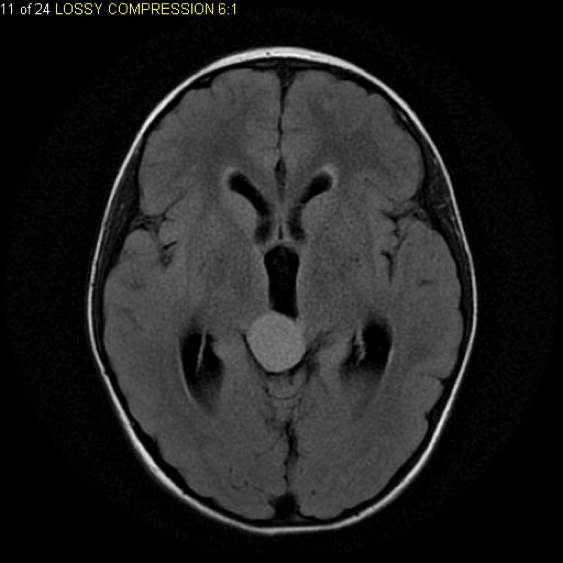

2. Medulloblastoma

- Origin: Neuroectodermal (germ cell-derived)

- Location: 4th ventricle, cerebellum

- Features:

- Obstructive hydrocephalus: morning headache, vomiting

- Gait instability, diplopia, cerebellar signs

- Treatment: Surgical resection + radiation + chemotherapy

- Prognosis: Poor (70% 5-year survival; CSF spread common)